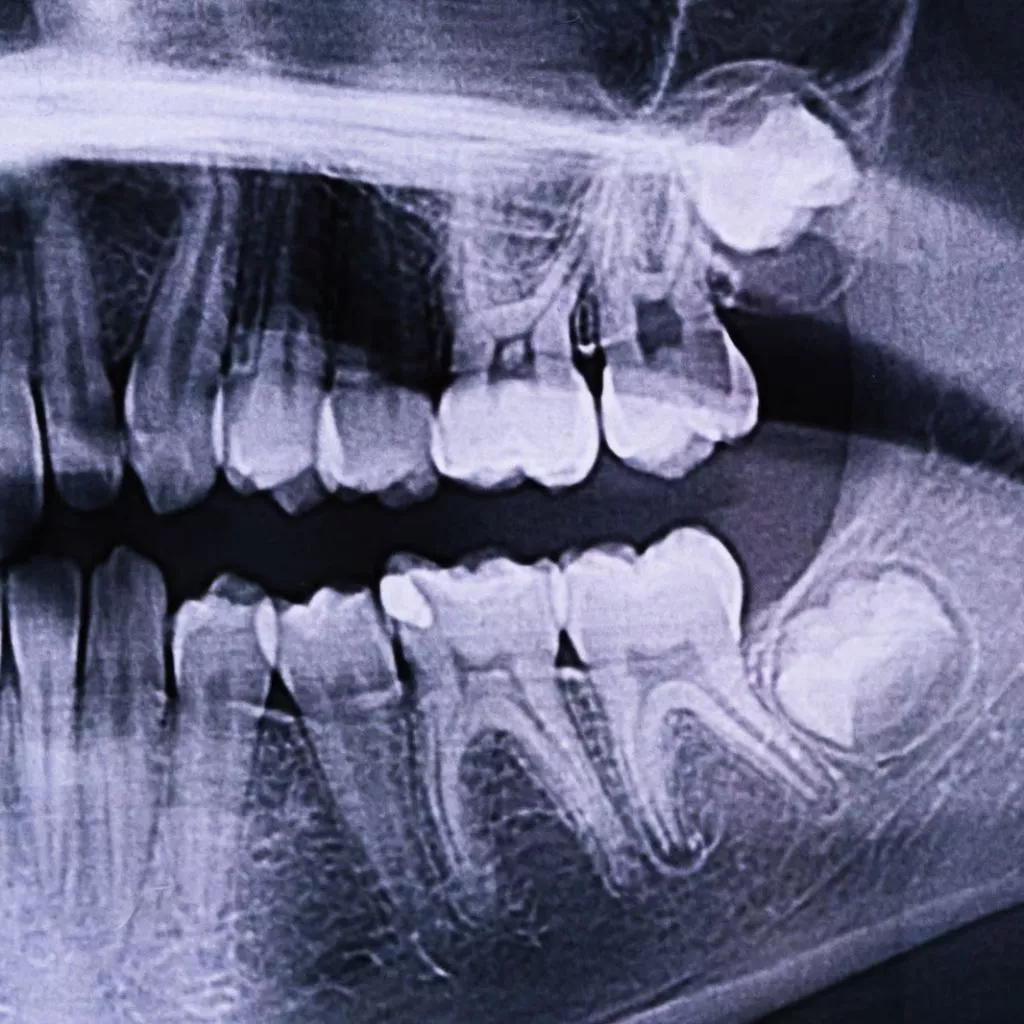

En Channel Islands Family Dental, utilizamos imágenes dentales intraorales de última generación para ofrecer evaluaciones precisas y detalladas de su salud oral. Esta avanzada tecnología nos permite capturar imágenes de alta calidad de sus dientes y encías, lo que permite planes de tratamiento precisos y personalizados. Visite nuestras ubicaciones en Oxnard, Santa Paula, Ventura, Newbury Park y Port Hueneme para descubrir cómo la imagen dental intraoral puede mejorar su experiencia de cuidado dental.